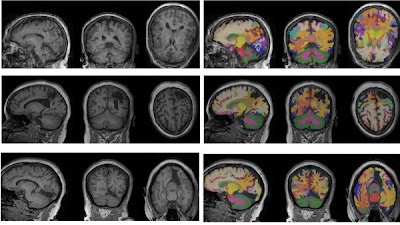

💡 Revolutionizing neuroimaging: DLMUSE segments brain MRIs in seconds, enabling large-scale studies without the need for complex setups -- Dive into the future of brain research! doi.org/10.1148/ryai.2… @NeurIPSConf #NeurIPS2025 #AI #DeepLearning